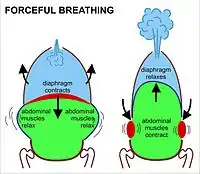

During heavy breathing (hyperpnea) as, for instance, during exercise, exhalation is brought about by relaxation of all the muscles of inhalation, (in the same way as at rest), but, in addition, the abdominal muscles, instead of being passive, now contract strongly causing the rib cage to be pulled downwards (front and sides).[8] This not only decreases the size of the rib cage but also pushes the abdominal organs upwards against the diaphragm which consequently bulges deeply into the thorax. The end-exhalatory lung volume is now less air than the resting "functional residual capacity".[8] However, in a normal mammal, the lungs cannot be emptied completely. In an adult human, there is always still at least one liter of residual air left in the lungs after maximum exhalation.[8]

Diaphragmatic breathing causes the abdomen to rhythmically bulge out and fall back. It is, therefore, often referred to as "abdominal breathing". These terms are often used interchangeably because they describe the same action.